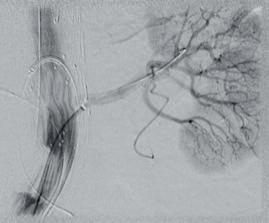

Radiolucent smart polymer © 2022 Shape Memory Medical Inc. All rights reserved. 807 Aldo Avenue, Suite 109, Santa Clara, CA 95054 USA +1.408.649.5175 | info@shapemem.com | www.shapemem.com Indications: The IMPEDE Embolization Plug is indicated to obstruct or reduce the rate of blood flow in the peripheral vasculature. The IMPEDE-FX Embolization Plug is indicated for use with the IMPEDE Embolization Plug to obstruct or reduce the rate of blood flow in the peripheral vasculature. Refer to the IFU – supplied with each device – for a complete statement of the indications, contraindications, warnings, and instructions for use. Inferior Mesenteric (IMA) and Renal Accessory Artery angiographic image courtesy of Alexander Maβmann, MD, Saarland University Medical Center, Homburg/Saar, Germany. The images are illustrative and do not represent the actual size of any products. Patent: www.shapemem.com/patents Shape Memory Medical products and associated components are not available in all countries or regions. Please contact your Shape Memory Medical representative for details regarding product availability. Shape Memory Medical and IMPEDE are registered trademarks of Shape Memory Medical.